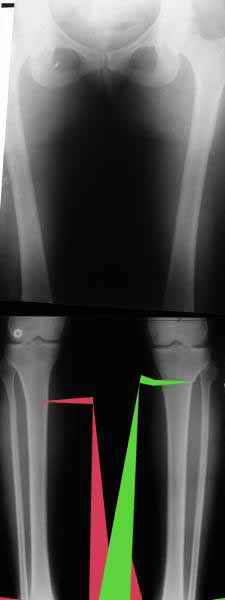

Из приведнной схемы не совсеим понял что означают разноцветные линии.

И зачем латерализация периферического фрагмента. Я всегда делаю медиализацию. См схему. И для данного случая медиализация подходит как нельзя лучше.

a> Я всегда делаю медиализацию. См схему. И для данного случая

Медиализация - это чисто эстетический прием, как я понимаю. Поскольку если делать остеотомию ниже вершины деформации, для восстановления оси надо делать смещение по ширине, в данном случае как раз латерализацию.